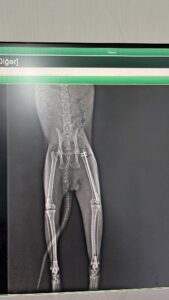

This cat, who lived in Kenan Aral’s garden, had its hind leg broken after being hit by a car and underwent surgery today at Cadde Clinic. He is currently recovering. Please support us so we can help this cat and our beloved companions in similar situations.